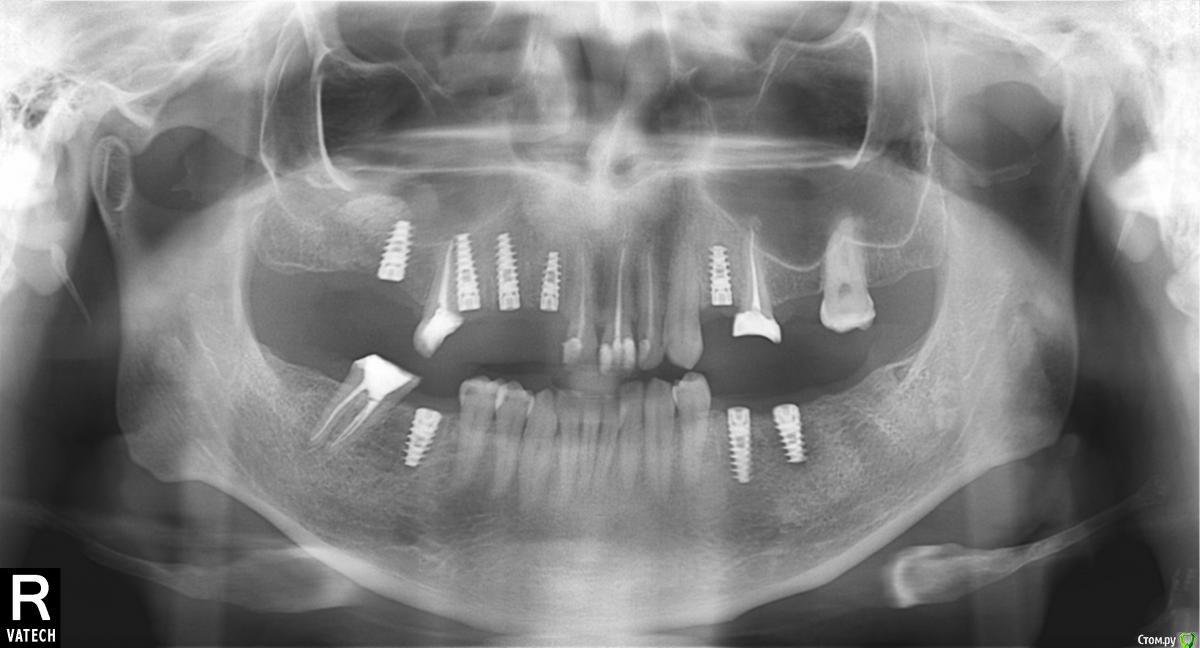

66666 Опубликовано 26 апреля, 2015 Поделиться Опубликовано 26 апреля, 2015 Еще лет 20 назад заметил, что прикус у меня в течении дня меняется. Потом я на это не обращал внимание, потерял много зубов и забыл об этом. За последний год было произведено масштабное удаление, лечение, имплантация и протезирование и я вспомнил об этой проблеме. Последний снимок был сделан до протезирования и даже в том состоянии я это замечал. Меня это совершенно не беспокоит, я привык к новым зубам, но мой врач думает, что это его косяк и каждый раз предлагает мне подточить коронки. Выглядит это так, с утра и примерно до обеда соприкасаются все зубы, позже только передние и крайние правые. И при всем желании я не могу сомкнуть зубы левых челюстей. Есть повод для беспокойства? Ссылка на комментарий

66666 Опубликовано 30 апреля, 2015 Автор Поделиться Опубликовано 30 апреля, 2015 не надо так спорить) почитал чем занимается гнатолог. ничего не понял. мой лечащий врач разводит руками и не понимает на что я жалуюсь. пожевав капирку след контакта есть, но я его не ощущаю. получается, что зазор не велик. а последнии дни так вообще все нормально. от чего зависит не понял... ps: примерно пол года назад на мой снимок откликнулся в лс некий врач с этого форума и поинтересовался не беспокоит ли меня моя челюсть. я был очень удивлен этому вопросу. а оказалось, что на снимке видно, что суставы у меня какие то странные. Ссылка на комментарий

faity Опубликовано 30 апреля, 2015 Поделиться Опубликовано 30 апреля, 2015 ну то что проблема у вас есть, вы видимо давно в курсе. теперь смотрите в интернете что такое артрит и артроз височно-нижнечелюстного сустава и думайте искать спеца или нет Ссылка на комментарий